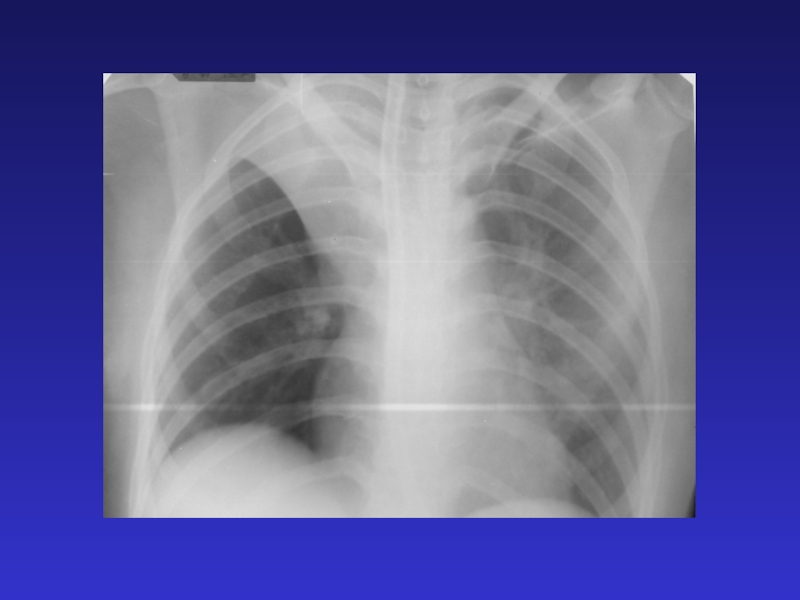

Слайд 15ТОТАЛЬНОЕ И СУБТОТАЛЬНОЕ ЗАТЕМНЕНИЕ

Причины: - воспалительный заболевания легких (пневмония, туберкулез) - жидкость

в плевральной полости; - ателектаз; - отек; - цирроз; - опухоль; - фиброторакс (только для

тотального)

ТОТАЛЬНОЕ И СУБТОТАЛЬНОЕ ЗАТЕМНЕНИЕПричины: - воспалительный заболевания легких (пневмония, туберкулез) - жидкость в плевральной полости; - ателектаз;